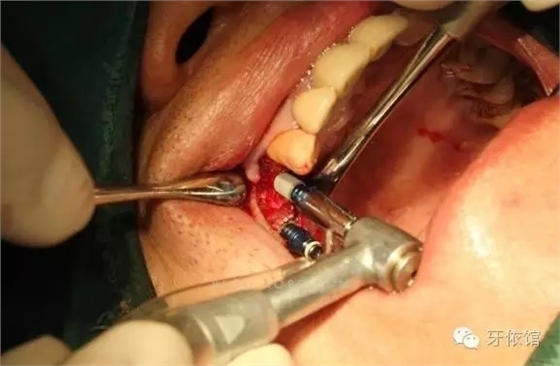

切開翻瓣

640.webp (1).jpg

右上4,6牙位定位,先鋒鉆鉆至距離上頜竇底1-2mm處,改用CAS鉆穿透一個(gè)窩洞竇底。